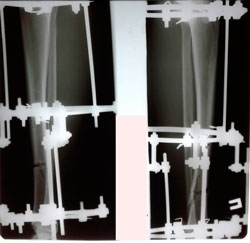

Исходник - 21 год.

Дата операции - 22.09.2020